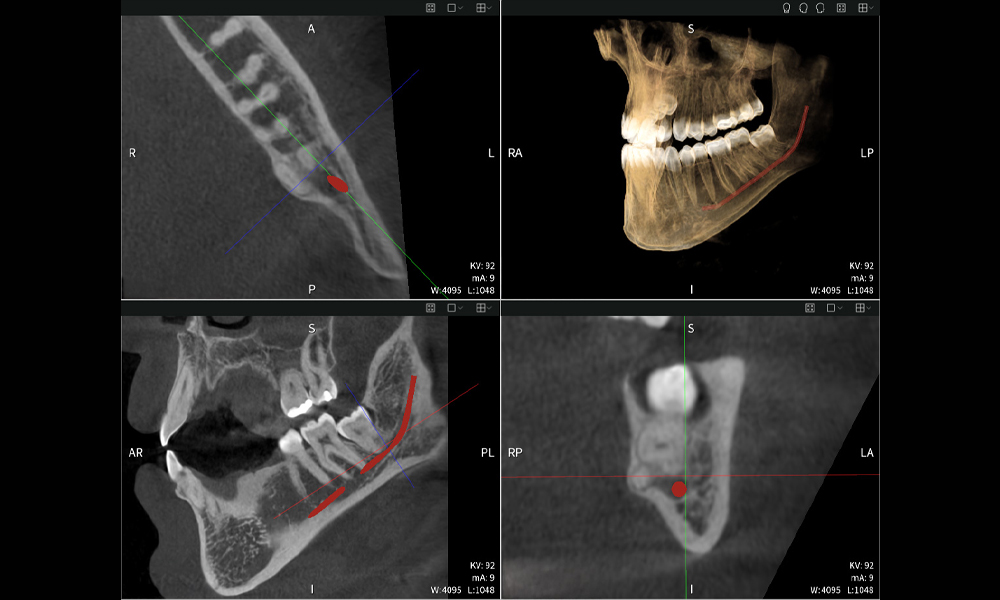

Below you will find a case from Dr. med. dent. Oliver A. Centrella, in which the CBCT images obtained with Seethrough Max provided crucial information on the complex anatomy and the critical relationship between the wisdom teeth and the inferior alveolar nerve. In this case, there is a indication for the surgical removal of the wisdom teeth.

Figure a

- Top left: Axial cross-section of the left mandible (region 38) showing the inferior alveolar nerve (red) in proximity to the roots of tooth 38.

- Top right: 3D reconstruction of the entire mandible for orientation. The red-marked inferior alveolar nerve illustrates its location within the jawbone.

- Bottom left: Sagittal view of the mandible (region 38), highlighting the close spatial relationship between the roots and the nerve canal.

- Bottom right: Coronal view of the mandible (region 38), which is crucial for assessing the spatial position of the roots relative to the nerve.